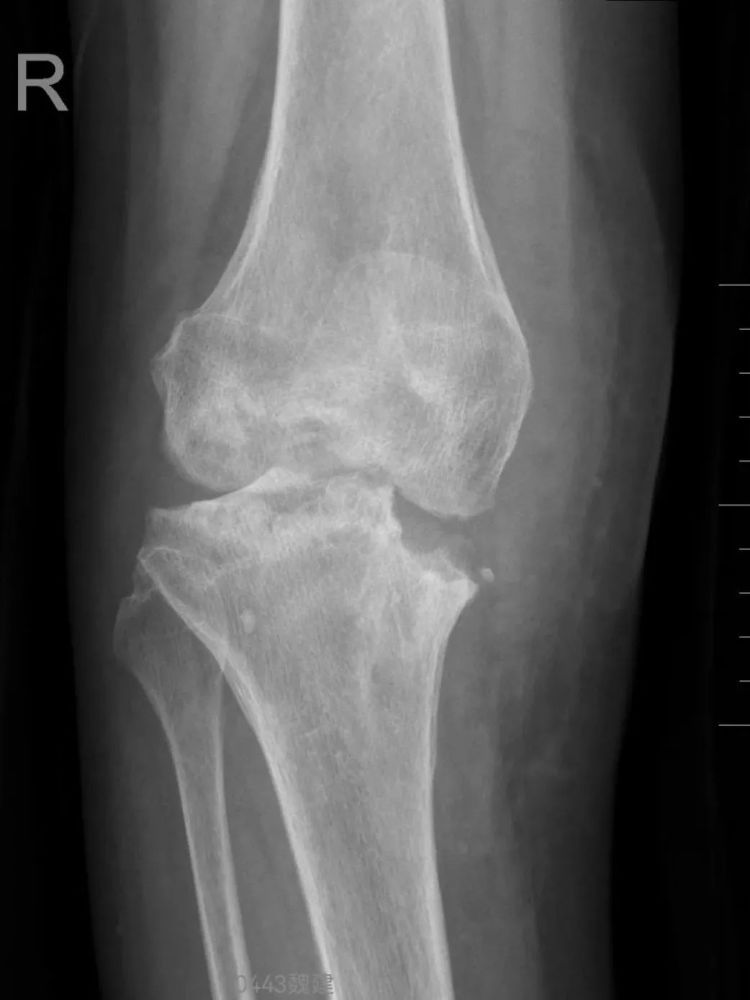

医生告诉她,干骺端骨质严重破坏,关节稳定性丧失,已发展为安德森Ⅱa型骨缺损。传统抗结核药物、常规清创术及常规关节置换手术难以恢复关节功能,日常生活将会受到极大影响。

膝关节结核是一种由结核分枝杆菌引起的慢性骨关节感染性疾病,属于肺外结核的常见类型。若未能早期诊断和治疗,病情可能进展至晚期,导致关节严重破坏甚至残疾。

安德森分型Ⅱa型即为膝关节结核的晚期阶段之一,其特点是明确的骨质破坏和关节结构改变,但尚未合并广泛脓肿或窦道形成。

安德森分型是国际上广泛使用的骨缺损分型系统,膝关节结核患者多伴有骨质缺损,其中Ila型主要表现为:

➤单侧髁部骨缺损;

➤关节间隙狭窄或消失;

➤关节周围可能出现局限性脓肿。

医生提醒,此阶段若未及时干预,疾病会继续发展,导致关节完全强直或下肢畸形。

膝关节结核早期症状隐匿,易被忽视。若出现膝盖反复肿痛、活动受限、关节畸形等症状,千万不要大意!尤其伴随低热、盗汗、消瘦等情况,赶紧排查结核,若不及时干预,可能面临关节强直、融合的风险。